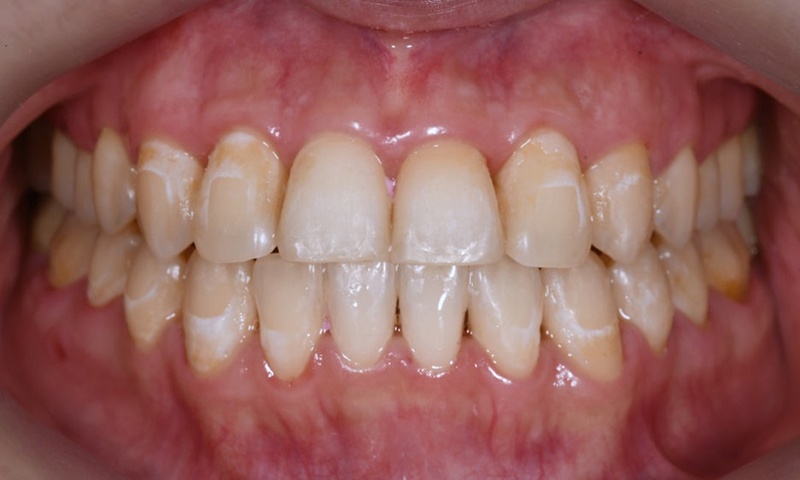

Before & After photos of ICON Treatment

The patient was very satisfied with the outcome. Treatments for white spots often provide high satisfaction, as these spots are long-standing concerns, even if others don’t notice them. If white spots on your front teeth are troubling you, we recommend visiting Yonsei JW Dental Clinic for evaluation and treatment.